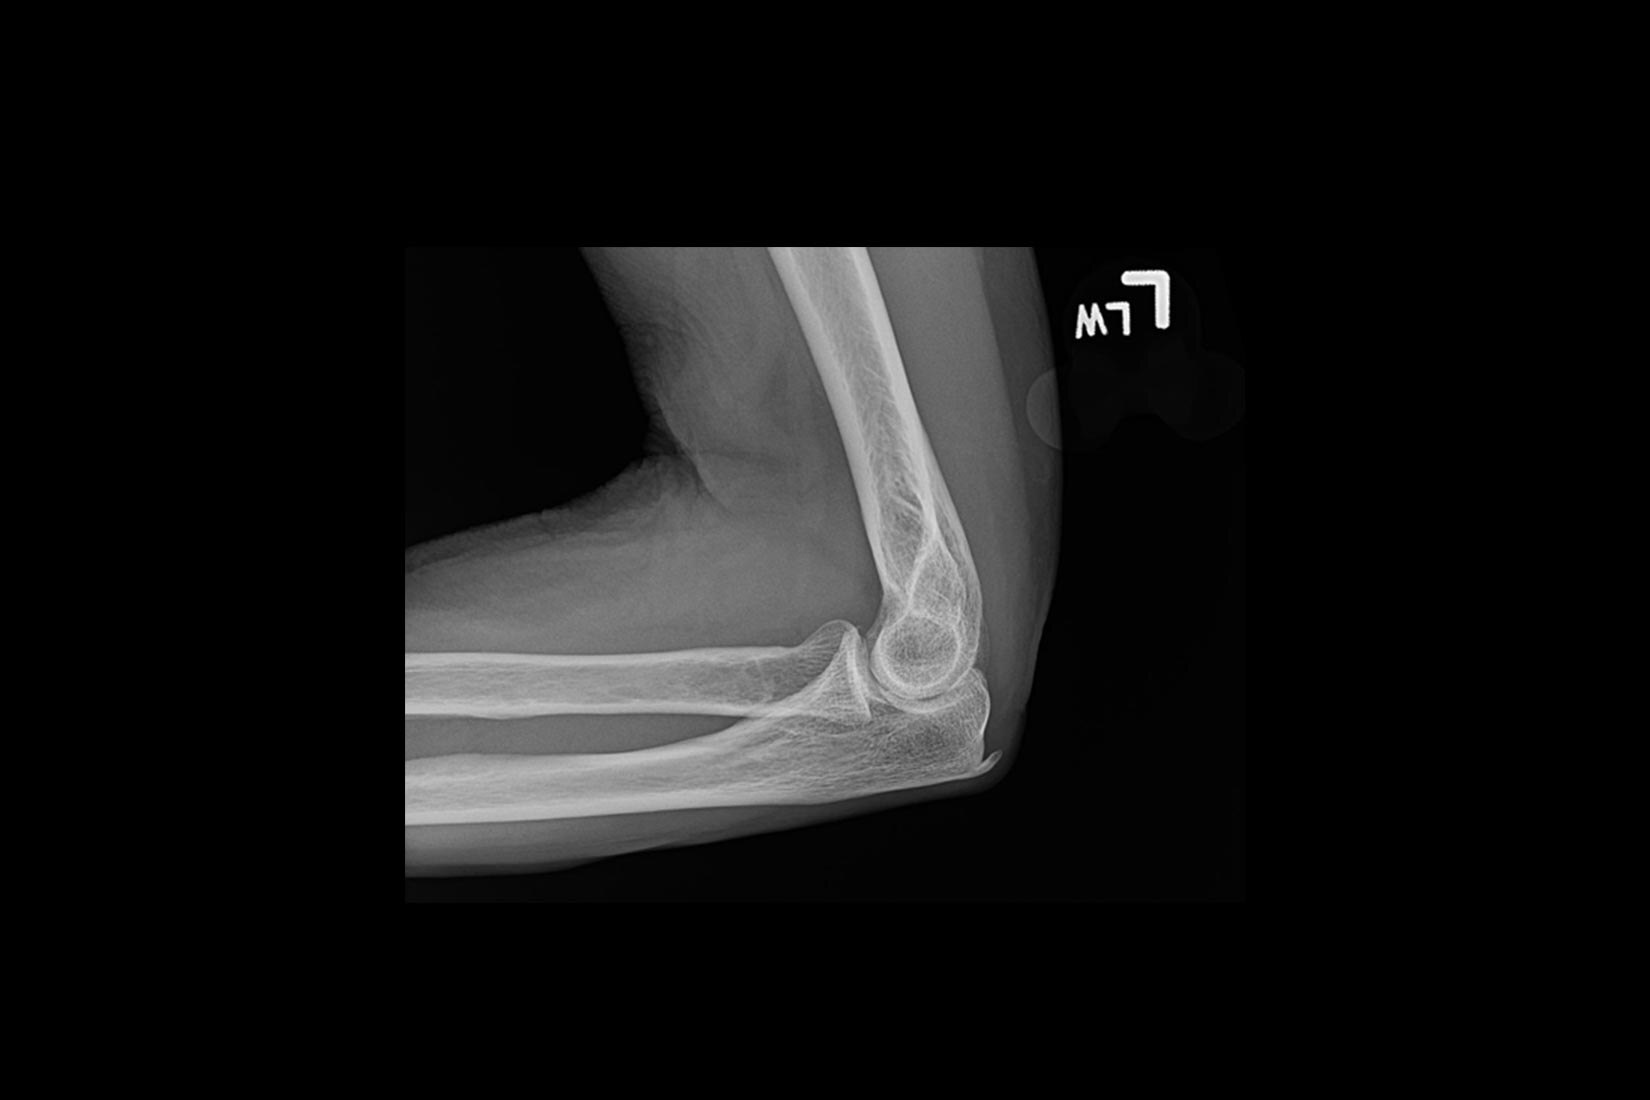

Üstün görüntü kalitesi

Daha net görüntüler daha kolay tanılar anlamına gelir ve derin öğrenme teknolojimiz AIR™ Recon DL ile olağanüstü kalitede görüntüleri daha hızlı elde edebilirsiniz. Çok çeşitli anatomiler için en net sonuçları sağlayarak MR görüntülerini görüntüleme biçiminizde devrim yaratır.

Ayrıca, göz yorgunluğunu azaltabilen okunması kolay, yüksek kaliteli taramalarla elde ettiğiniz görüntülerin kalitesinden daha emin olarak oluşturulan raporların daha iyi bir genel deneyime sahip olmasını sağlayabilirsiniz.